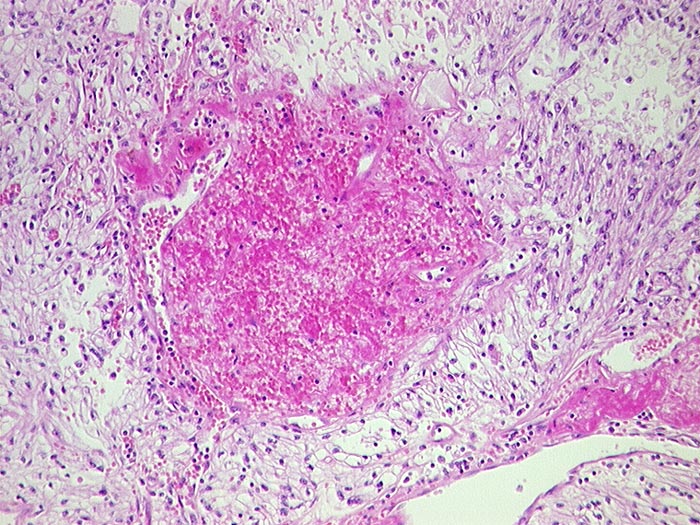

Hellzelliges Nierenzellkarzinom, FNP

Die Tumorzellen sind in der Regel etwa zweimal so gross wie normale Tubulusepithelien. Zytoplasma ist reichlich vorhanden, blass und vakuolisiert. Hyaline intrazytoplasmatische Einschlusskörperchen können gelegentlich vorhanden sein. Die Zellkerne sind abhängig vom Differenzierungsgrad unterschiedlich gross und atypisch. Die Grösse der Nukleolen schwankt entsprechend von unscheinbar bis sehr gross. Histiozyten, Nebennierenrindentumoren oder normale Nebennierenrindenzellen können aufgrund ihrer ähnlichen Zytomorphologie ein hellzelliges Karzinom vortäuschen. Der Nachweis von Drüsen, Papillen oder reichlich Glykogen spricht eher für das Nierenkarzinom.